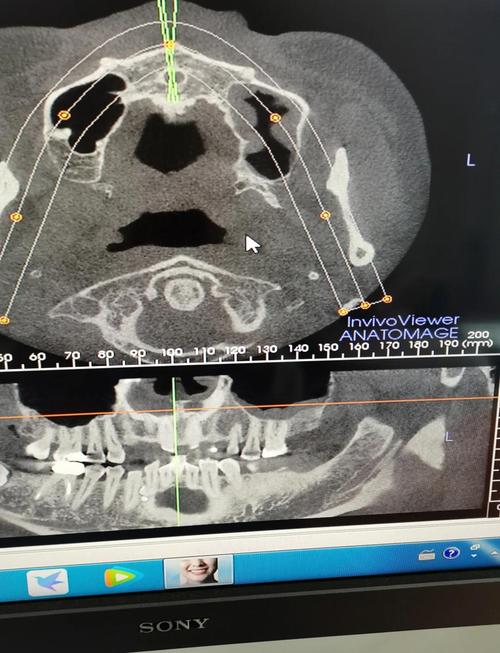

正畸治疗的核心是调整牙齿位置、改善咬合关系、协调颌骨发育,这需要全面了解牙齿排列、牙根形态、牙槽骨状况、颌骨大小与位置关系,以及面部软组织轮廓,仅通过口腔检查或模型分析,无法获取骨骼、牙根等深层结构信息,而X光影像能提供“全景视角”:例如全景片(曲面断层片)可观察全口牙齿的萌出方向、牙根长度、是否有埋伏牙或牙根吸收;头颅侧位片能测量骨骼角度、牙齿与颌骨的相对位置,用于制定精准矫治方案;复杂病例可能还需CBCT(锥形束CT)获取三维数据,评估骨量、牙根与神经管关系等,这些影像是正畸诊断的“导航仪”,直接关系到治疗方案的合理性和效果。